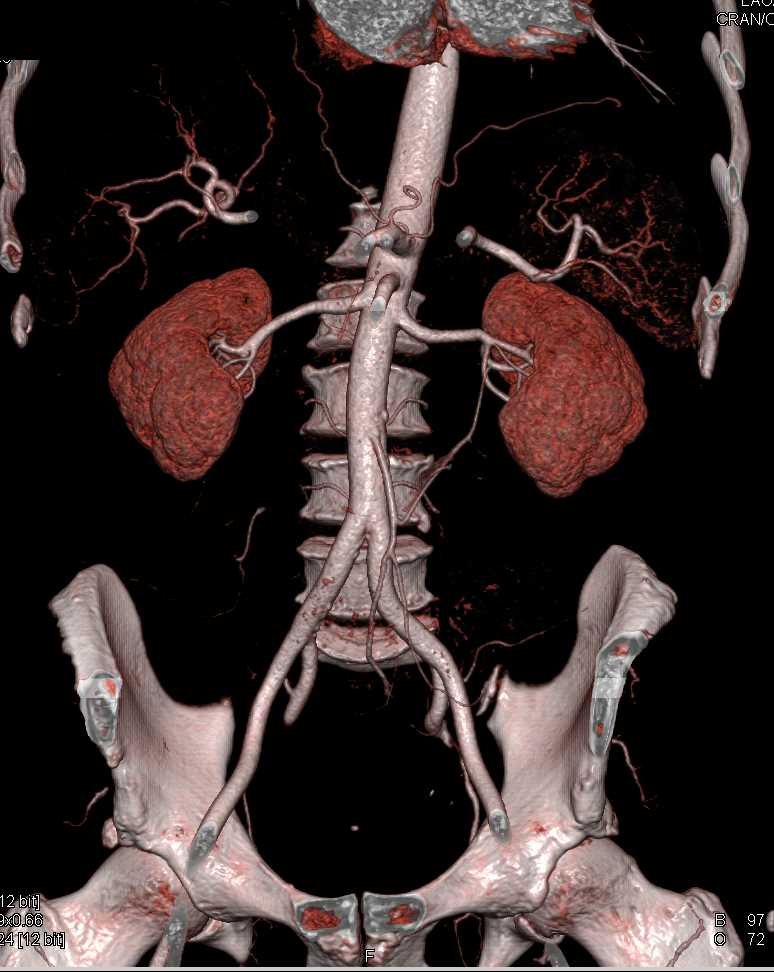

Carcinoid Tumor with Desmoplastic Reaction